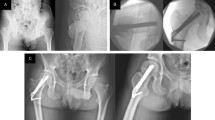

MANY cases of fractures of the neck of the femur are complicated by death of the femoral head. Similarly, a large number of cases of necrosis of the femoral head follows on traumatic dislocation of the hips. The earlier this important complication can be diagnosed the better can treatment be planned.